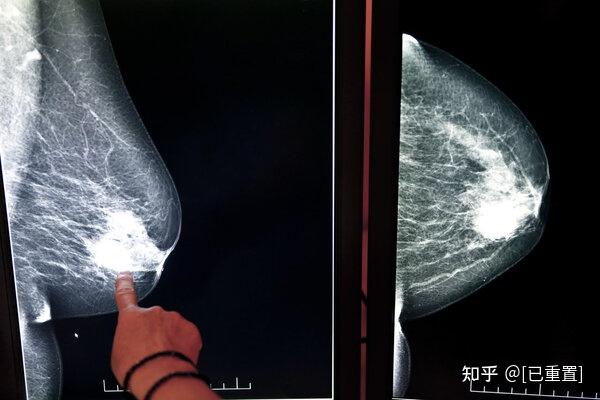

第一,无痛单发的小肿块,很多人常常在无意间触摸到小肿块,遗憾的是,很多人并没有引起重视,她们误把乳腺癌当成了小叶增生,结果可想而知,随着时间的推移,肿瘤很可能会发生转移。

第二,局部隆起,随着肿块越来越大,可以引起局部隆起,这个时候,往往能够发现左右不对称,如果这个时候,你依然不重视,肿瘤将很快发生远处转移。

事实上,大部分乳腺癌的患者,可能都是第一种表现,如果这个时候,你没有及时触摸到异常的肿块,或者触摸到也没有引起重视,就可能导致乳腺癌不断进展。

后面三种表现相对比较突出,遗憾的是,有些乳腺癌,并不会出现这些症状。